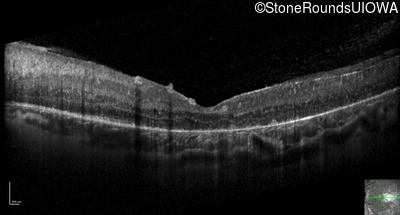

Optical Coherence Tomography - Left - 20/80 -1

Exemplar / OCT Stack

OCT Stack